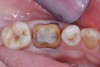

A 61-year-old female patient presented with a failed alloy restoration and missing the entire lingual surface of tooth No. 19 (Figure 2 and Figure 3). The argument could have been made to use either an onlay or a crown to replace the affected tooth. With the extent of the missing tooth structure, the malocclusion, and the patient's history of bruxism, treatment with a full-coverage restoration was selected to maximize longevity.

(2.) Preoperative images.

Figure 2

(3.) Preoperative images.

Figure 3